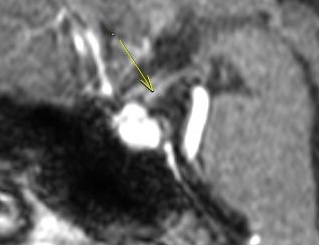

Lymphocytic hypophysitis, an inflammatory disorder of the pituitary stalk and gland, can cause multiple hormone deficiencies. The disease is considered to be of autoimmune etiology. We report here a case of lymphocytic hypophysitis with cortisol deficiency in an 18-year-old female who had been previously diagnosed with neurofibromatosis type 1. The case study also discusses the role of neurofibromin gene in autoimmunity and possible pathogenesis.